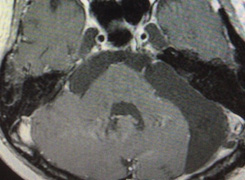

聴神経腫瘍は小脳と脳幹(橋と呼ばれる部分)の間にあるわずかな隙間で、小脳橋角部と呼ばれる場所にできます。この狭い部分に聴神経(音を感じる神経と平衡感覚の神経が混ざっています)、顔面神経(顔を動かす神経)、三叉神経(顔の感覚を伝える神経)、舌咽神経・迷走神経(ものを飲み込んだり声を出すのに関係する神経)、外転神経(眼を外側に動かす神経)に加えて、椎骨動脈という太い動脈やその枝が存在しています。小脳は体のバランスやいろいろな動作を調節しています。脳幹には、運動や感覚神経の通り道(障害されると麻痺や手足の感覚障害が生じます)や意識をつかさどる中枢などがあり、また生きていくために必要な機能に直接関係しているということです。さらに髄液(脳の中や周りを満たしている水のような液体)の通り道がすぐ近くにあります。このため、良性腫瘍とはいえ、大きくなると様々な症状を呈し、中には重篤になることがあります。

- 頭部MRI/MRA:CTより感度が高く診断力に優れています。また、造影剤を使わなくてもCTより感度が高く診断できます。CT同様、造影剤を使うと腫瘍は造影されはっきりと描出されます。